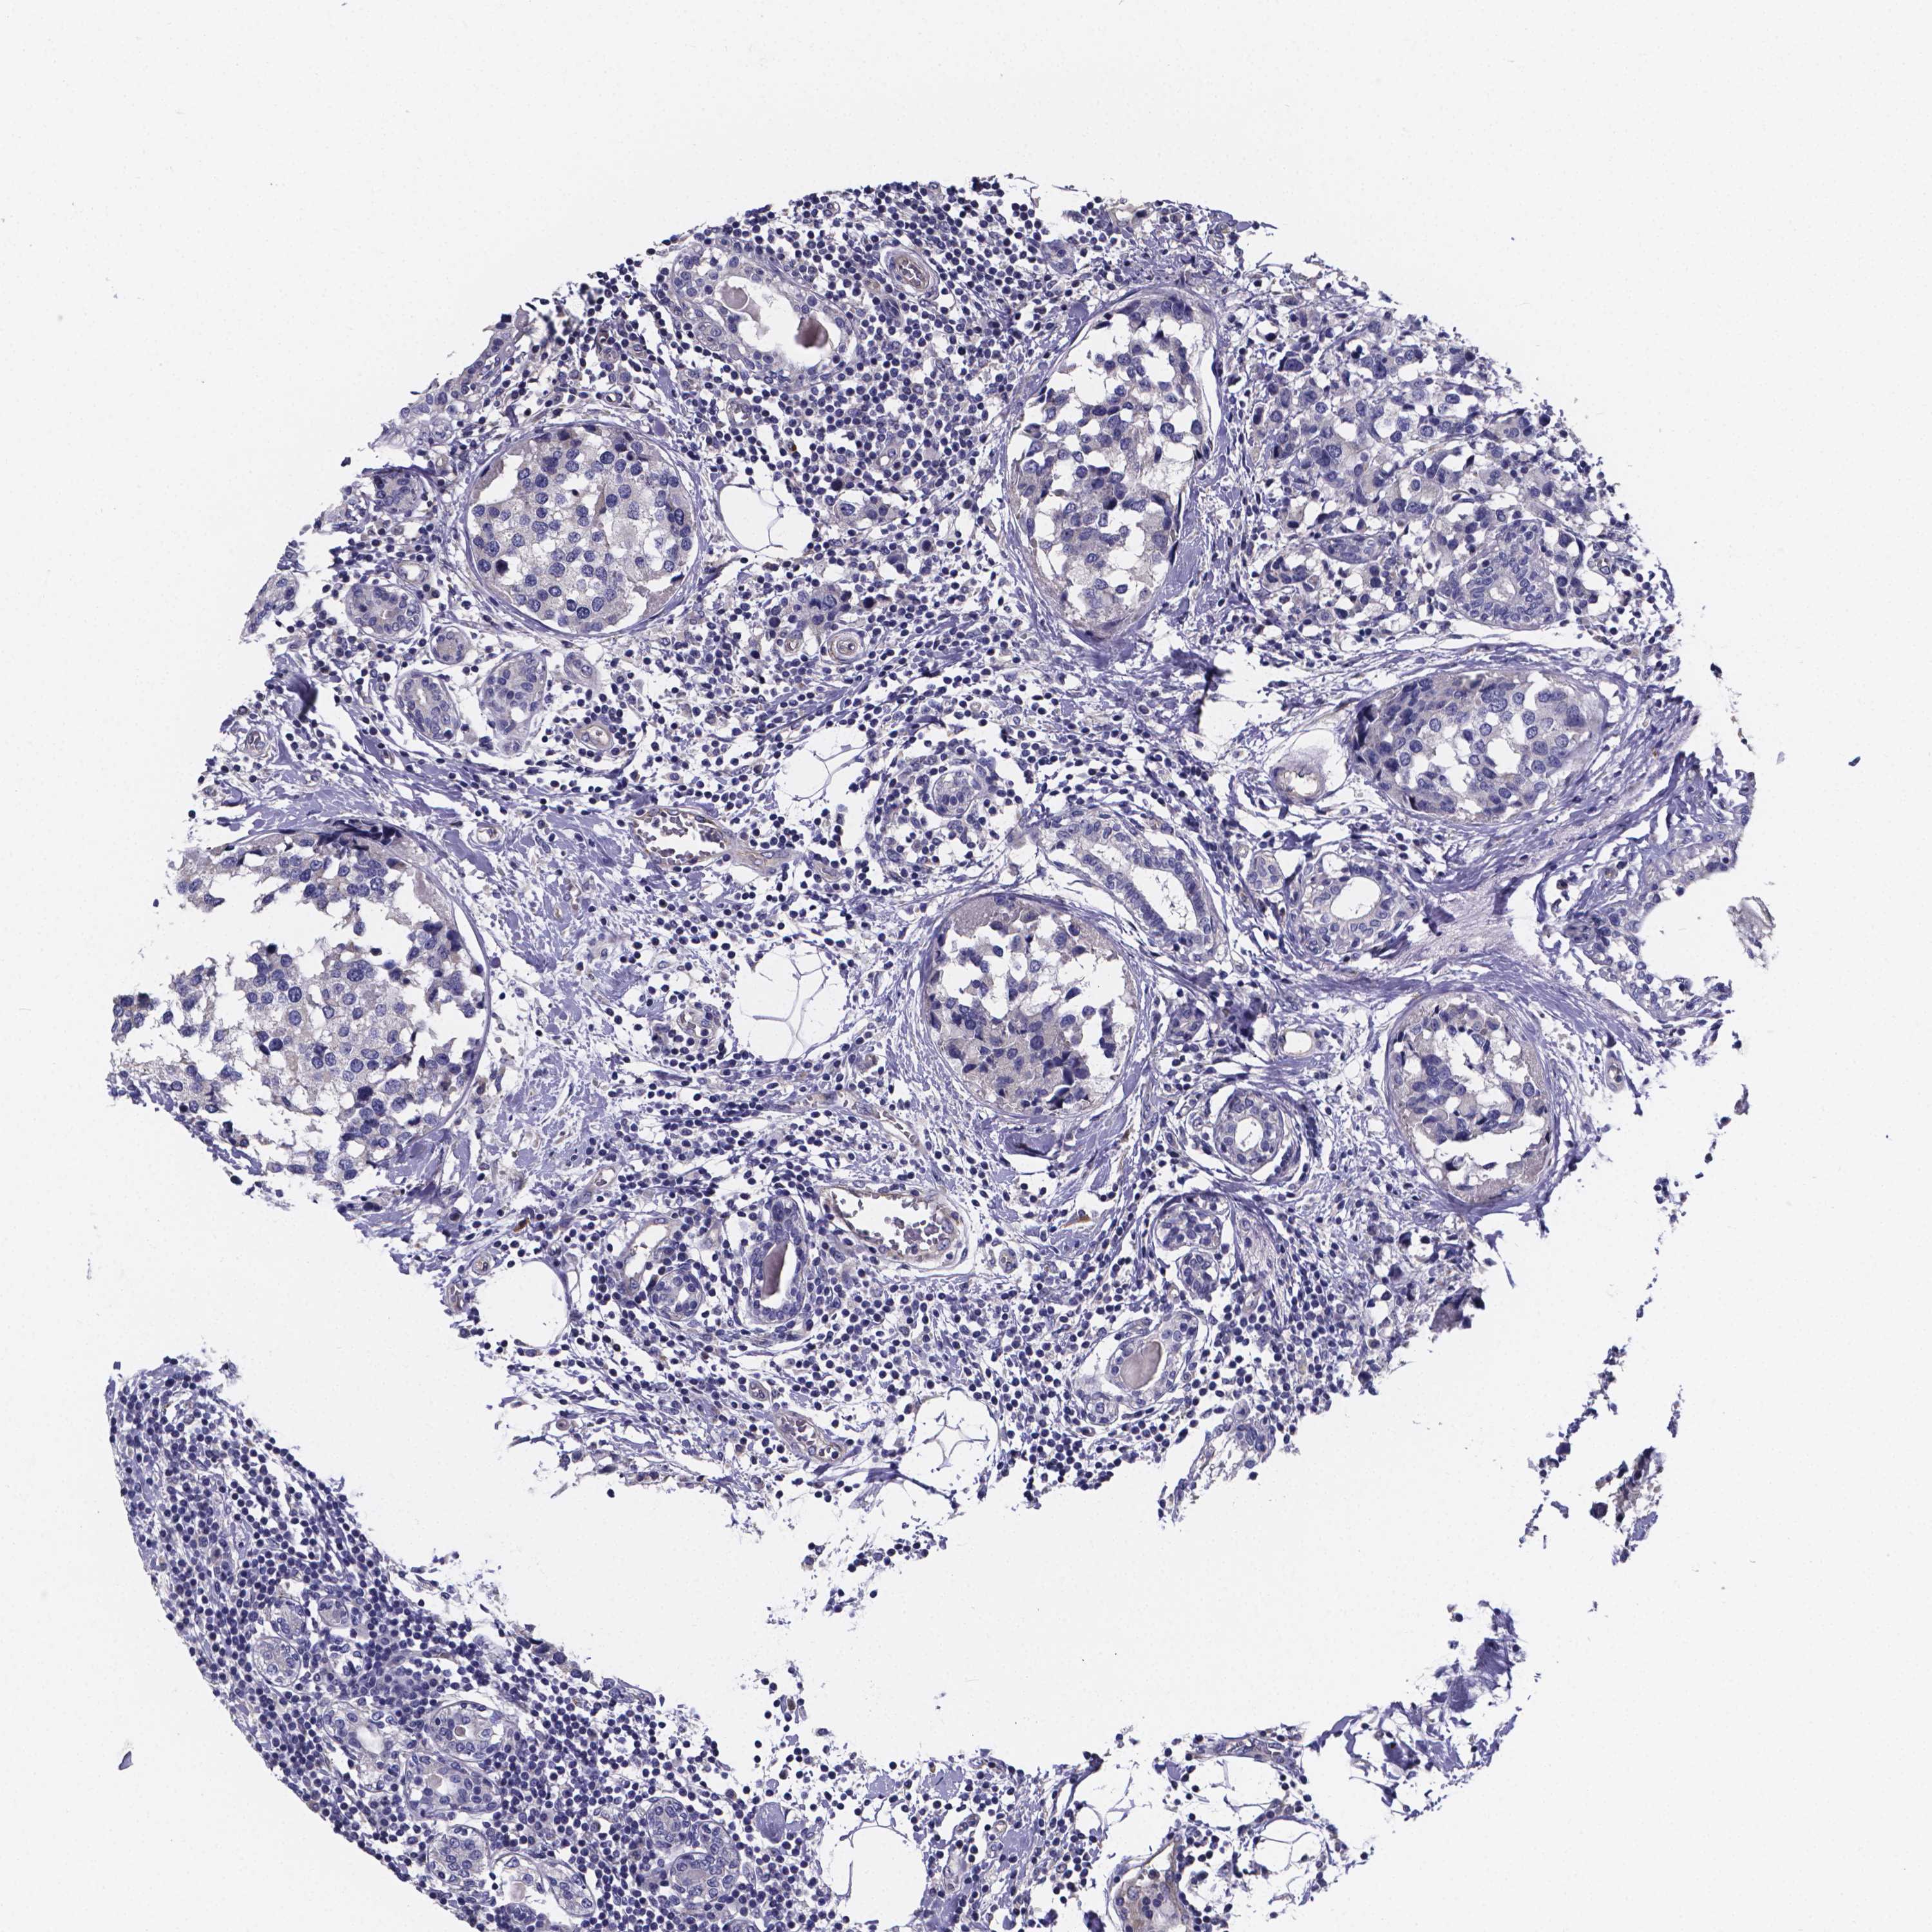

BRCA TCGA BRCA VALIDATION PROTEIN EXPRESSION